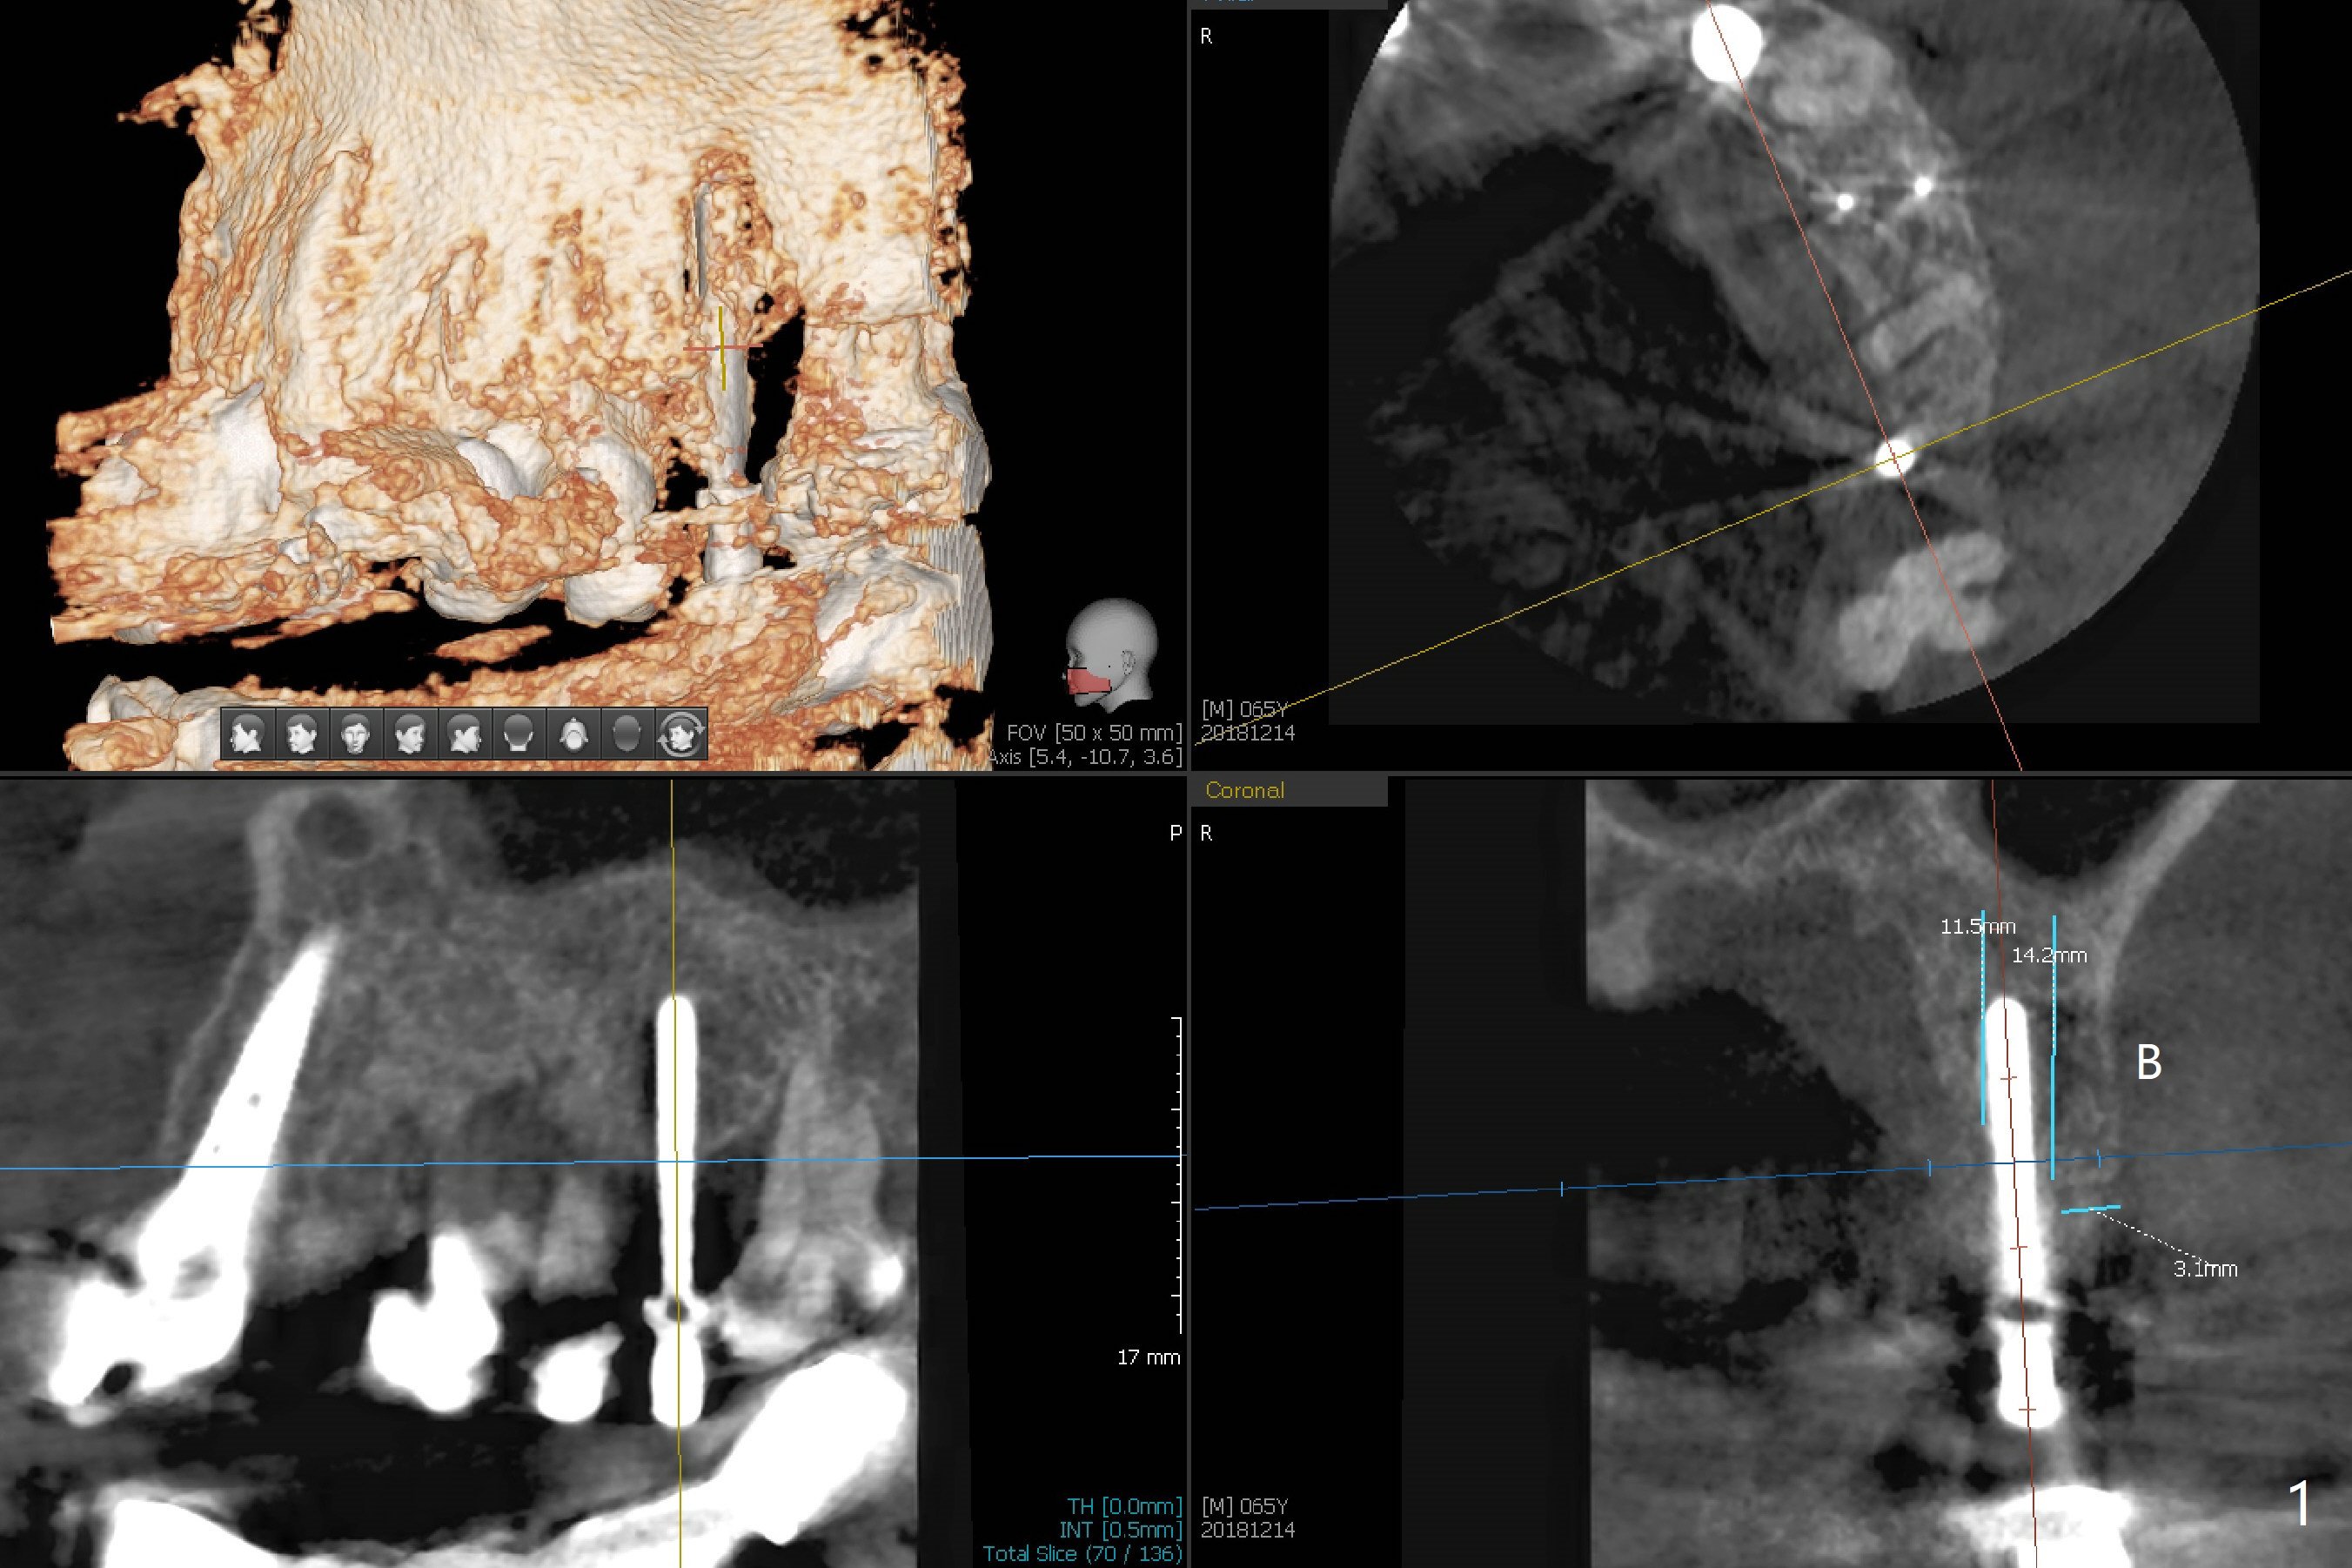

Eight-month limited ortho including use of a 1-piece implant (Fig.3 P (ball type)) as a distal anchor increases the mesiodistal space of #14 from <4 mm to 6 mm (near premolar width).  Guided surgery is not indicated because of presence of brackets and band and the narrow space.  Also due to the latter, incision is difficult to make.  In stead a 3.5 mm tissue punch is applied.  After 2.2 mm drill, a parallel pin is placed; it appears that the initial osteotomy is palatal (Fig.1).  Lindamann bur is adopted to move the osteotomy buccal.  The last drill (3 mm for 3.5 mm implant) has no resistance when it enters the buccalized osteotomy.  A longer implant than designed is placed (3.5x13 mm, Fig.2,3, close to the sinus floor (dashed yellow line) with 50 Ncm.  When the implant osteointegrates, it will be used a mesial anchor to distalize the 2nd molar.